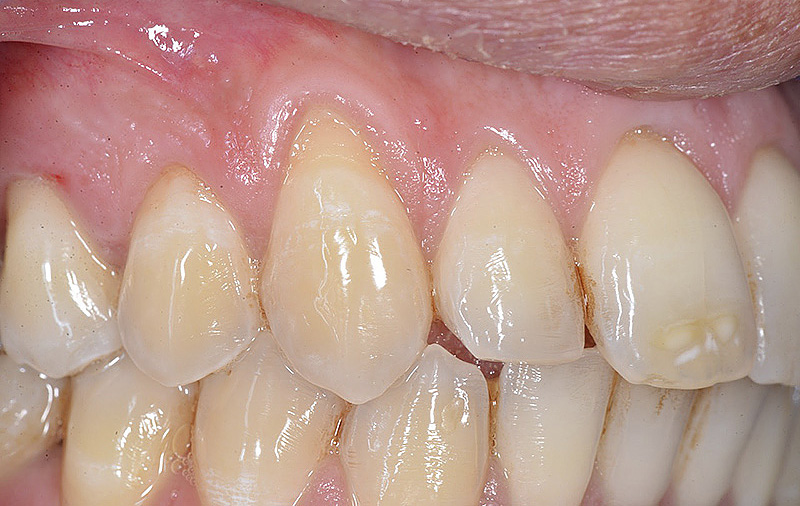

PREMESSA: in seguito all’estrazione dell’incisivo laterale superiore di destra, resasi necessaria per cause batteriche, si decide di affrontare il caso con il posizionamento di un impianto in sostituzione dell’elemento mancante dopo guarigione del sito infetto. Con tecniche rigenerative sia dei tessuti ossei mancanti a causa dell’infezione pregressa, sia dei tessuti gengivali che appaiono inizialmente troppo spostati in alto, si ripristina una corretta morfologia delle parabole (contorni) gengivali e delle papille interdentali (triangoli di gengiva tra due denti vicini).